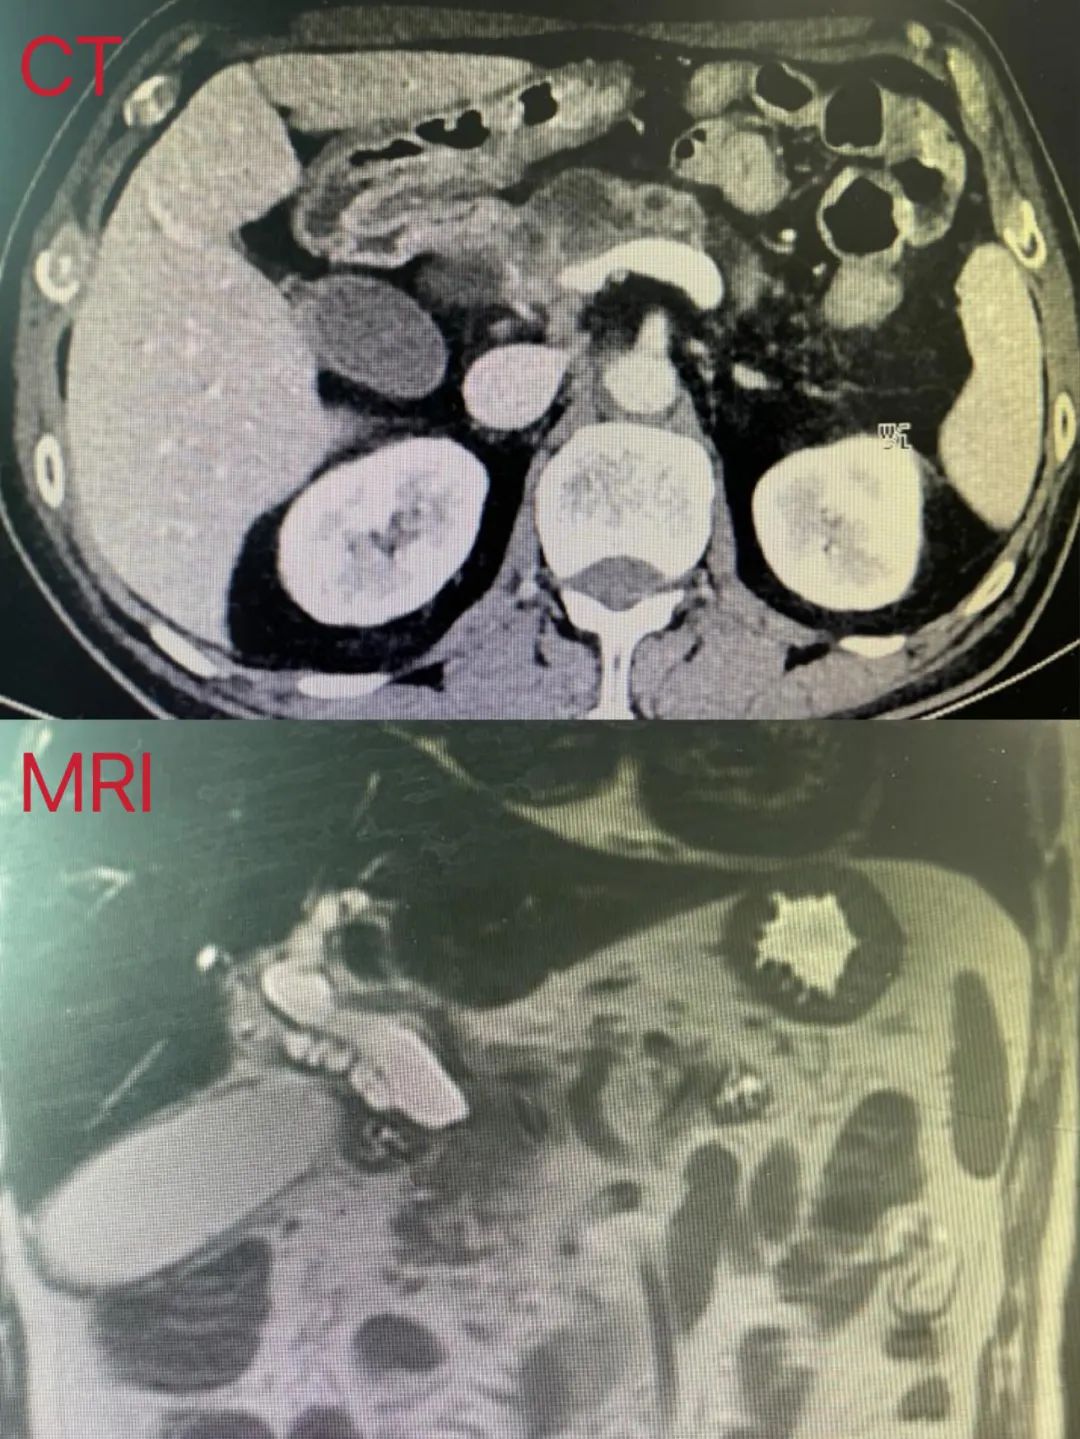

患者为高龄男性,因“间断性腹痛伴皮肤巩膜发黄1周余”入院,入院后完善相关检查提示:胰头肿瘤侵犯门静脉,考虑胰头癌,胰体囊肿,梗阻性黄疸。在与患者及患者家属充分沟通后,决定为其行腹腔镜下胰十二指肠切除术+联合门静脉部分切除血管吻合重建+胰体切除术,最大程度保留了胰腺功能,使患者得到根治性治疗。现患者恢复良好,术后1周复查超声重建门静脉血流通畅无狭窄。